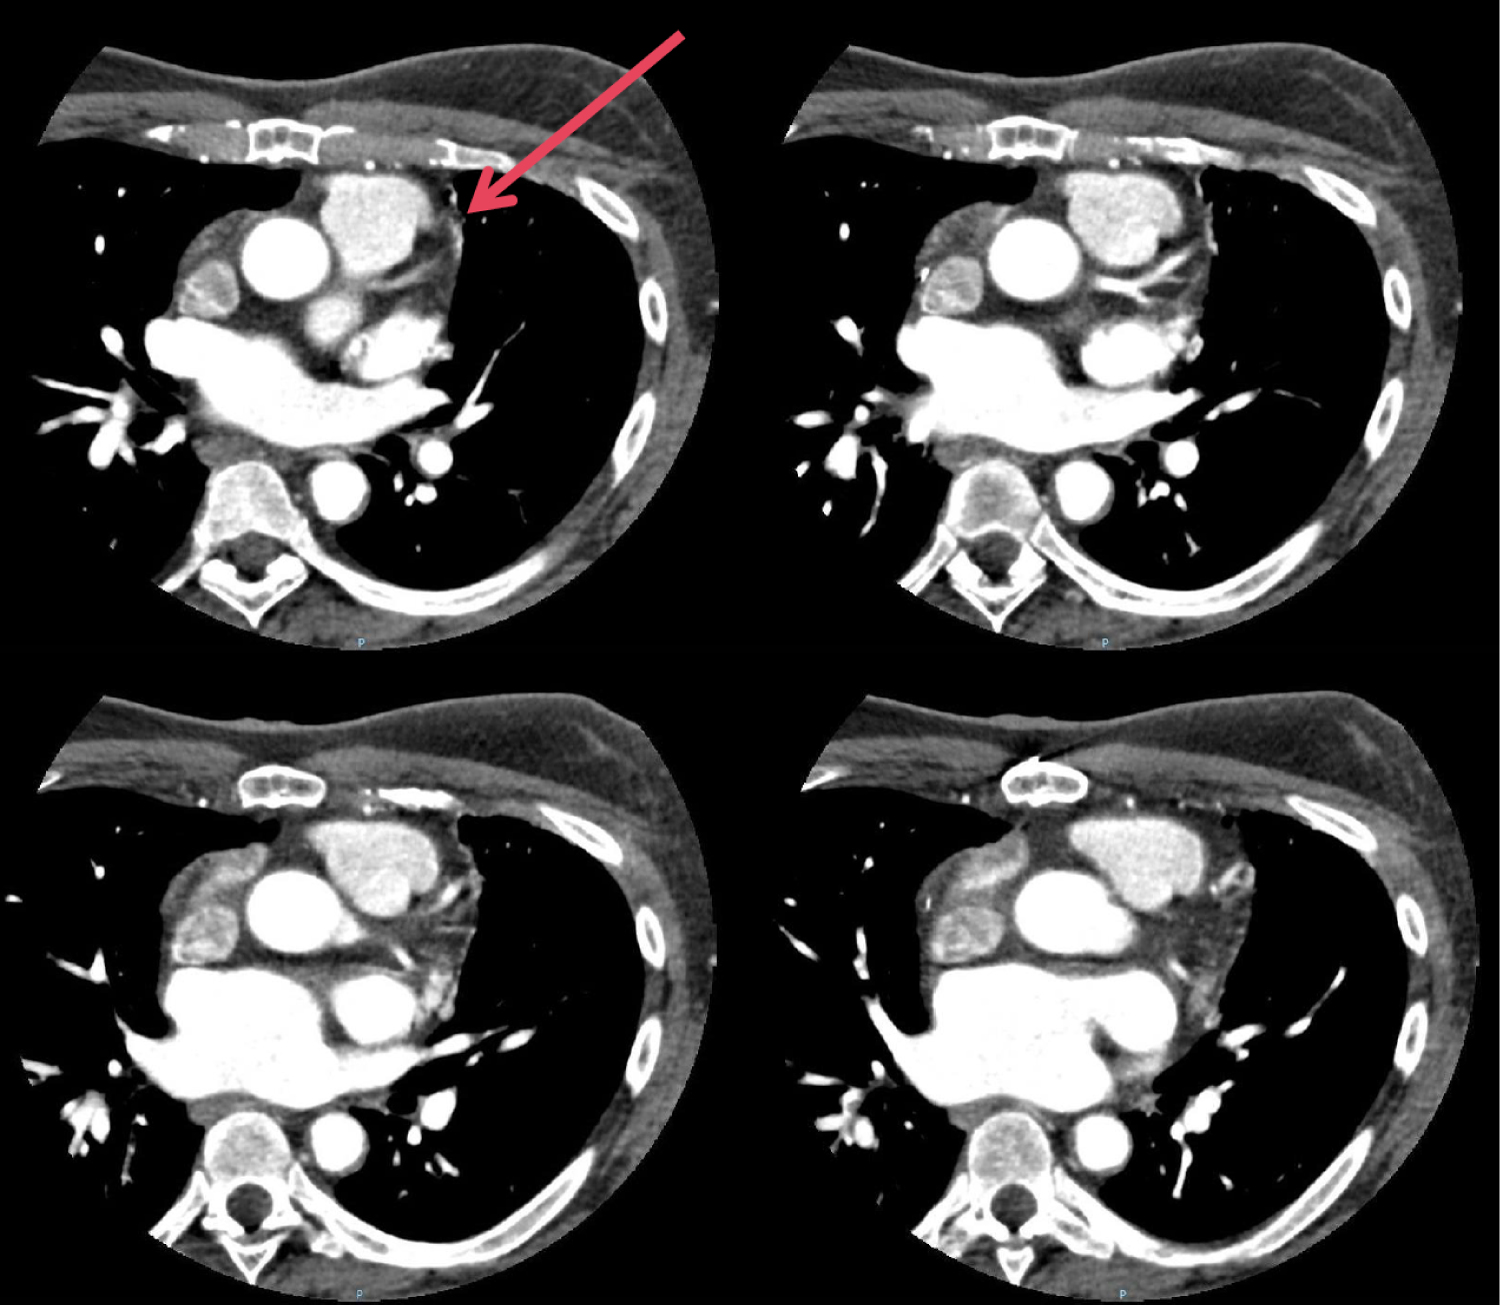

A CT coronary angiogram (Figure 1 and Figure 2) showed no significant luminal disease in all three coronary arteries; however, the presence of small vessels originating from the left anterior descending (LAD) artery which extended to the pulmonary trunk, suggestive of small fistulae extending from the coronary artery to the pulmonary artery.

Figure 1: The coronary artery-pulmonary artery fistulae (arrowed) seen on CT coronary angiogram. View Figure 1